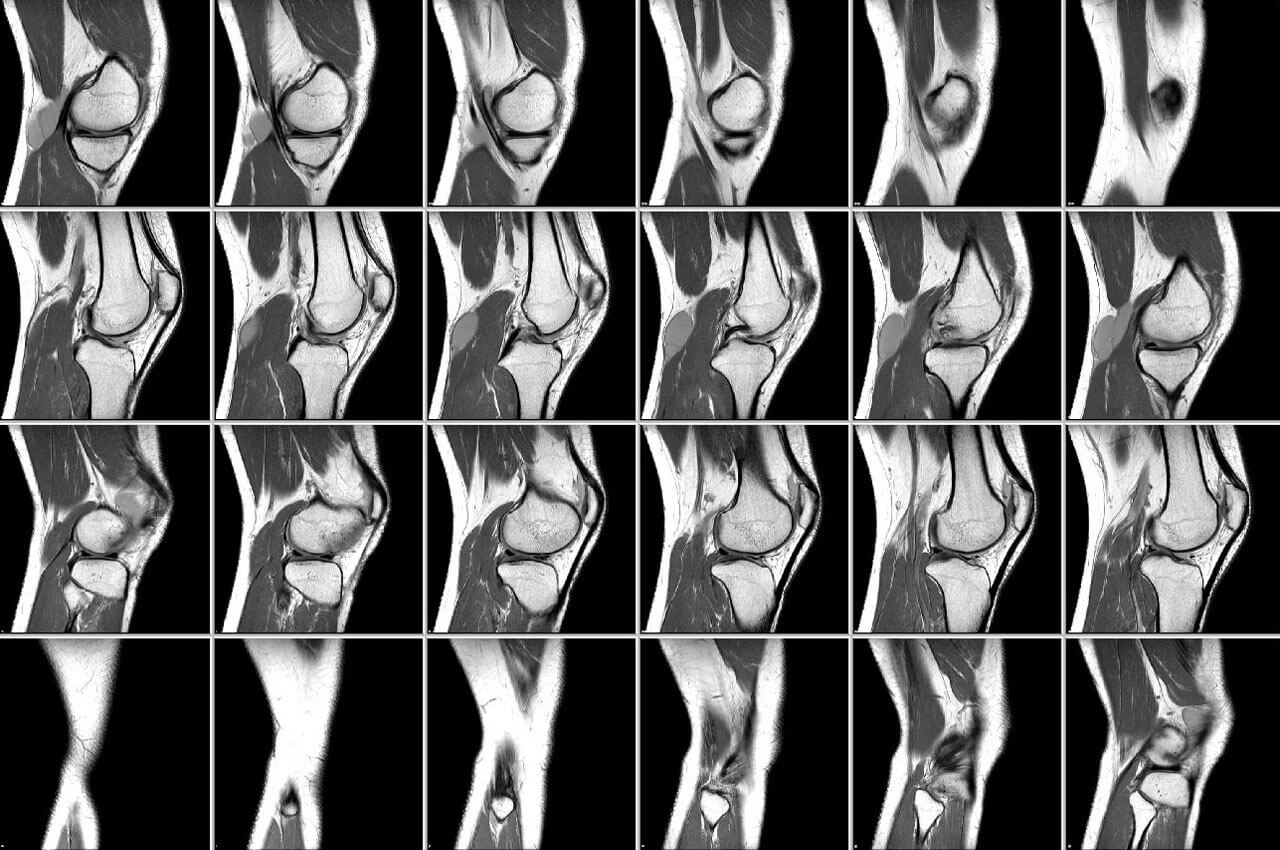

МРТ диагностика основана на действии ядерно-магнитного резонанса. Когда осуществляется магнитно резонансная томография коленного сустава, организм подвергается электромагнитному воздействию, в результате чего меняется положение атомов водорода. Этот эффект фиксируется аппаратом, который преображает полученные импульсы в трехмерное изображение.

Проведение МРТ целесообразно для определения состояния мягких тканей. Такое исследование отчетливо показывает изменения в суставе, что помогает в диагностике болезни или повреждения.

Целесообразность проведения такого дорогостоящего обследования определяет доктор. Ведь в некоторых случаях, действительно можно обойтись проведением УЗИ. Конечно, магнитная томография более детально фиксирует структуру сустава. К тому же все данные записываются на диск, и расшифровку может сделать не только врач, проводивший исследование, но и другие медики. Тогда как при проведении УЗИ выводы делаются, основываясь на субъективном мнении доктора, проводившего диагностику.